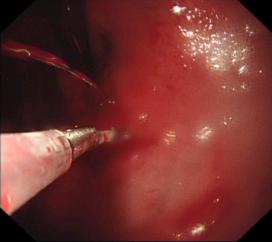

胃底溃疡并出血止血术